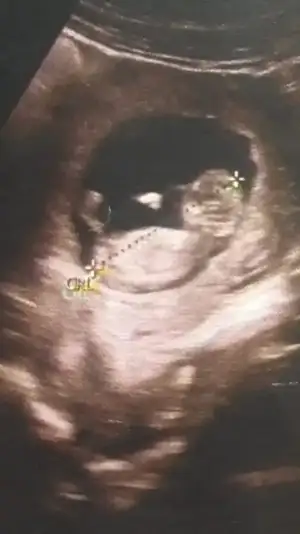

Canım bu 12 artı 4 dü burda doktor kıza benziyor yüzde 80 demişti

Eklentiler

• Screenshot_20210114-154037_Gallery.webp

Screenshot_20210114-154037_Gallery.webp

13,6 KB · Görüntüleme: 94